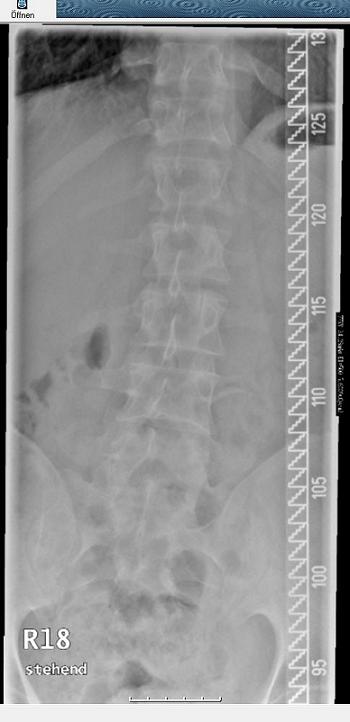

- Lendenwirbelsäule

- LWS stehend.jpg (27.64 KiB) 2505 mal betrachtet

Zuerst mal zu dem RöBi. Für mich sieht es so aus, als ob schon das Becken schief steht und die WS nicht gerade steht. Eigentlich sind im unteren Bereich nur mehrere sehr kleine, sich z.T. gegenseitig aufhebende Krümmungen zu erkennen. Durch den Schiefstand in der Beckenregion kommt die WS bis zur oberen BWS aus dem Lot, was durch eine mäßige (Gegen-) Krümmung von ca. 19° nur unvollständig ausgeglichen wird. Die Krümmung der oberen BWS wird wiederum durch eine Krümmung im BWS-HWS-Übergang kompensiert.